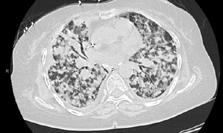

A 58-year-old female with recently diagnosed COVID-19 pneumonia was found to have a dry cough and dyspnoea in the setting of persistent bilateral hilar and mediastinal lymphadenopathy associated with bilateral nodular infiltrates. Of note, she immigrated to the USA from India 10 years prior, with the most recent travel to India 2 years ago. Quantiferon testing upon return to the USA was negative at that time. Workup included bronchoscopy with endobronchial ultrasound revealing non-caseating granulomas with negative stains for acid-fast bacilli (AFB). She was diagnosed with Stage 3 sarcoidosis and initiated on prolonged steroid taper with improvement of symptoms. With taper of steroid dose, however, she developed lymphocyte-predominant exudative effusion with negative cultures, and was reinitiated on a protracted steroid course with rapid symptom resolution. At 4-month follow-up, she had worsening CT findings upon steroid taper, and was started on azathioprine. One month later, she required hospital admission for worsening dyspnoea and fatigue. She was noted to be febrile, tachycardic, and tachypnoeic with worsening

hypoxia. Subsequent CT chest showed progression of bilateral nodular infiltrates with new right upper lobe consolidation and air bronchograms concerning for multifocal pneumonia (Figure 1). Incidentally, she was also noted to have calcified splenic granulomas. She developed rapid clinical deterioration, ultimately requiring mechanical ventilation, pressor support, and continuous renal replacement therapy. Repeat bronchoscopy revealed diffuse alveolar haemorrhage with multiple AFB smears positive for Mycobacterium tuberculosis. She was immediately initiated on quadruple therapy, but unfortunately, despite treatment, developed refractory shock and passed away 2 weeks after initial presentation.

A) Initial adenopathy with peripheral patchy ground glass opacities in the right lung following COVID-19 pneumonia. B) Persistent bulky adenopathy 1 year after initial presentation. C) Extensive nodularity throughout the right lung with increasing confluent opacities in the right upper lobe and stable mediastinal lymphadenopathy 2 years after initial presentation. D) Tuberculosis superimposed on sarcoidosis with progression of nodular infiltrates, worsening right upper lobe consolidation, and air bronchograms with incidental calcified splenic granulomas (not pictured).

Figure 1: CT progression of patient’s sarcoidosis and tuberculosis.